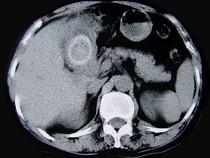

问题 女,55岁,右上腹痛多年,CT检查如图,最可能的诊断是 ( )

选项 A.胆囊胆固醇结石 B.胆囊胆红素结石 C.胆囊混合性结石并胆囊炎 D.胆囊癌 E.胆囊壁环状钙化

答案 C